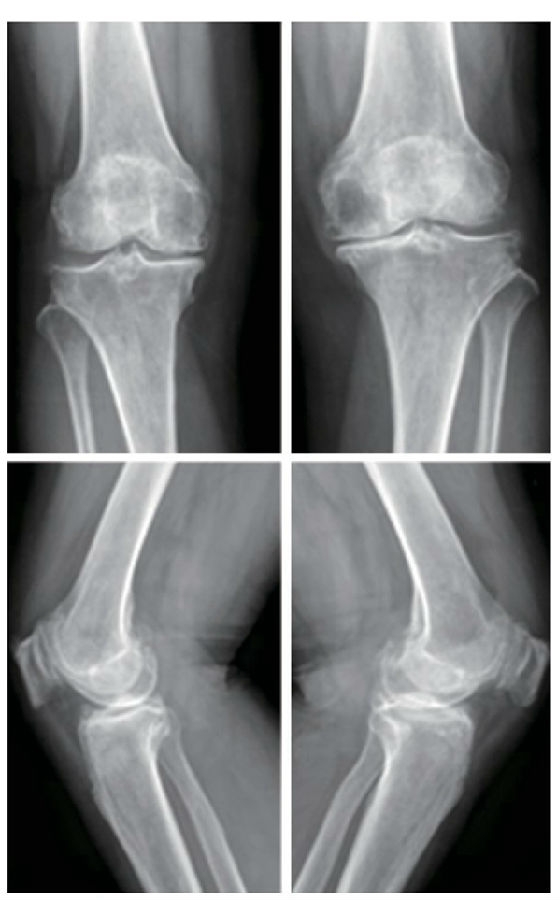

病例(1)65岁女性患者,因双膝关节疼痛伴活动 受限5年余入院。行双膝关节正侧位X线片可见典型前内侧骨关节炎表现,术前双下肢内翻排列,右膝HKA为4.26°,属于轻度内翻,左膝HKA为7.42°,属于中度内翻。术后3个月复查下肢力线右膝HKA为2.83°,左膝HKA为3.13°,较术前改善,手术前后影像学资料见图1~3。

图1 术前双膝关节正侧位X线片示双膝关节内侧间隙变窄